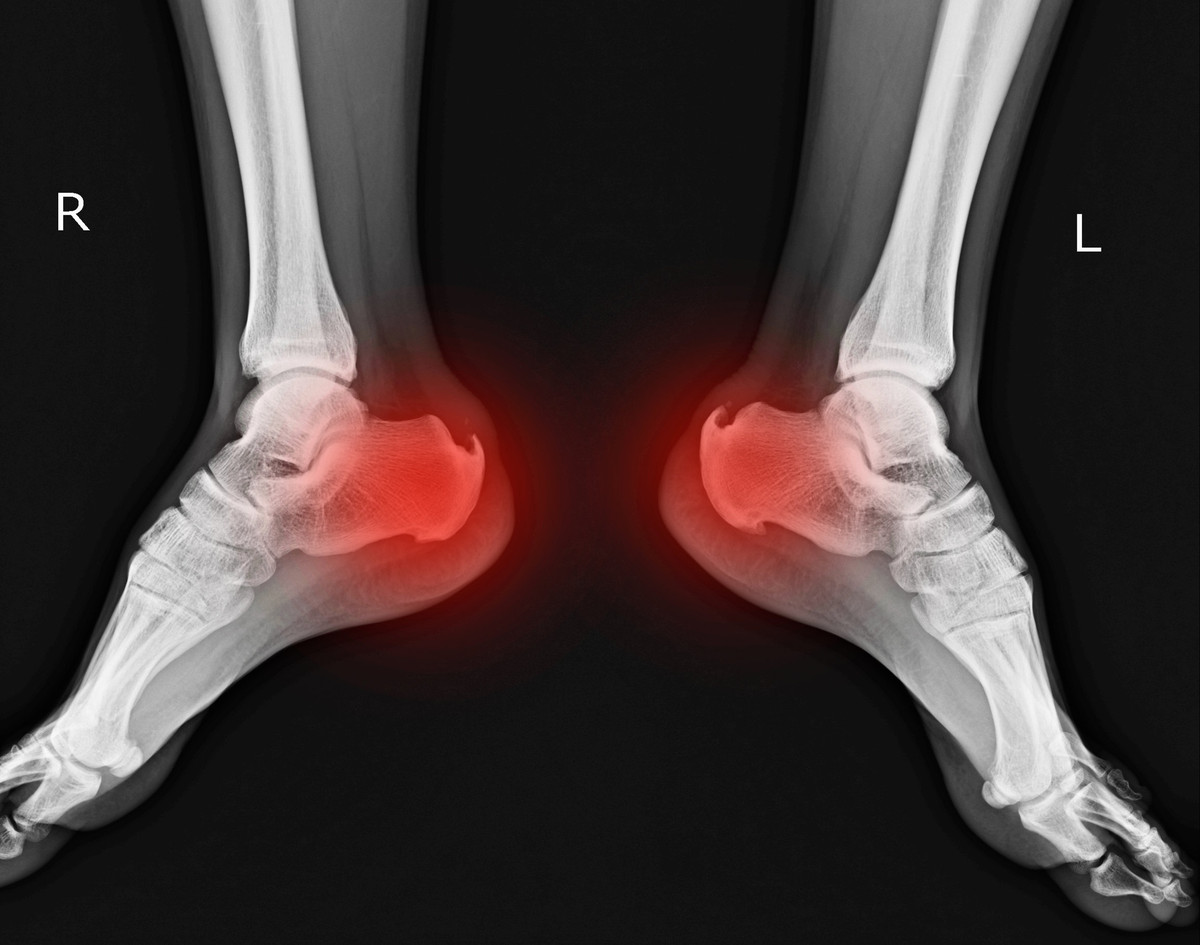

Did I Bruise Or Fracture My Heel The Orthopaedic Foot Ankle Center